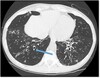

12

Q

What pathology is shown here? How do we know?

A

Cystic fibrosis

-Haziness inside the airway is the mucus, bronchiectasis (dilation of the airways)

How well did you know this?